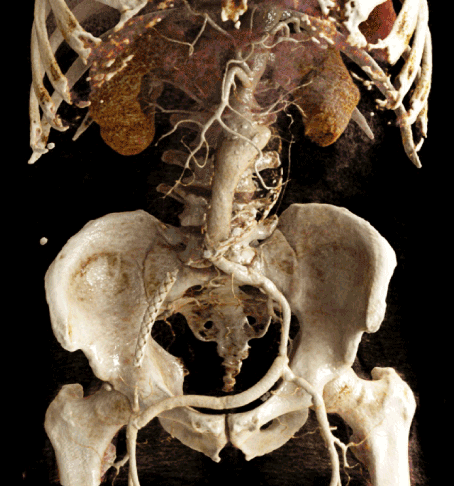

Figure 9. Postoperative Volume Rendering image

We present a case of a 78-year old male patient with an AAA involving the celiac trunk, the superior mesenteric artery and the renal vessels. As a norm variant doubled renal vessels on both sides were present. Regarding vascular medical history, a crossover bypass was made after an occlusion of the right common iliac artery. After discussion in the interdisciplinary vascular board, indication for endovascular repair was made. We decided to implant the fenestrated stentgraft through a single access via the left common femoral artery.

After surgical preparation of the left groin, a small-caliber renal artery on the left side was embolized with detachable coils (Interlock, Boston Scientific). After insertion of the individually designed fenestrated main graft tube (Anaconda, Terumo), blood flow to the remaining five visceral vessels – celiac trunk, superior mesenteric artery, left renal artery, superior and inferior doubled right renal artery – was maintained by insertion of covered stent grafts (Viabahn, Gore) through the fenestrations. Finally, an aortouniiliacal prosthesis was implanted (Anaconda, Terumo).

In the final angiogram and in the first postoperative CT-angiogram no early complications or endoleak were found. The peri- and postoperative course was uneventful. The patient was discharged in good general condition on the 7th postoperative day.